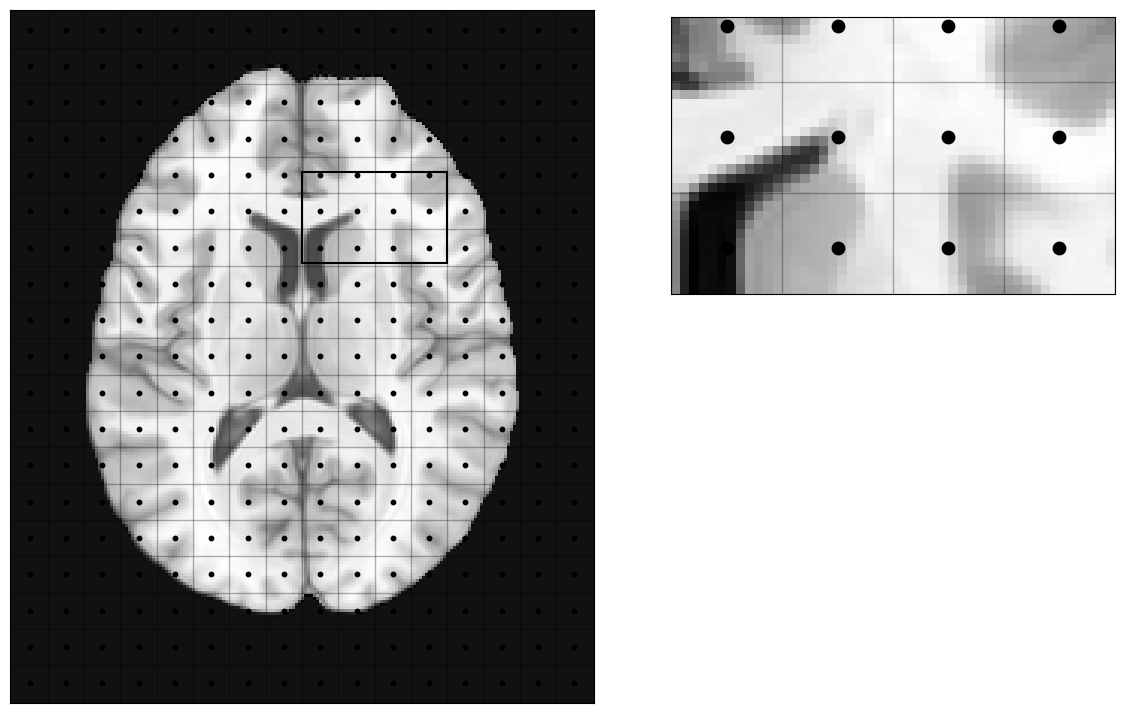

Sampling that brain and MRI

MRI will basically define an extent of phyisical space inside the scanner bore that will be imaged (field-of-view, Fov). That continuous space will be discretized into a number of voxels, and the signal corresponding to each voxel (a voxel is a volume element) will be measured at the center of the voxel (blue dots in the picture).

Which means, this discretization of the space inside the scanner will be imposed on the imaged object (a brain in our case):